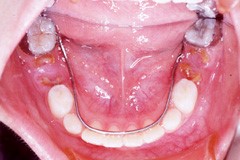

臼齒的保鏢─溝隙封填劑